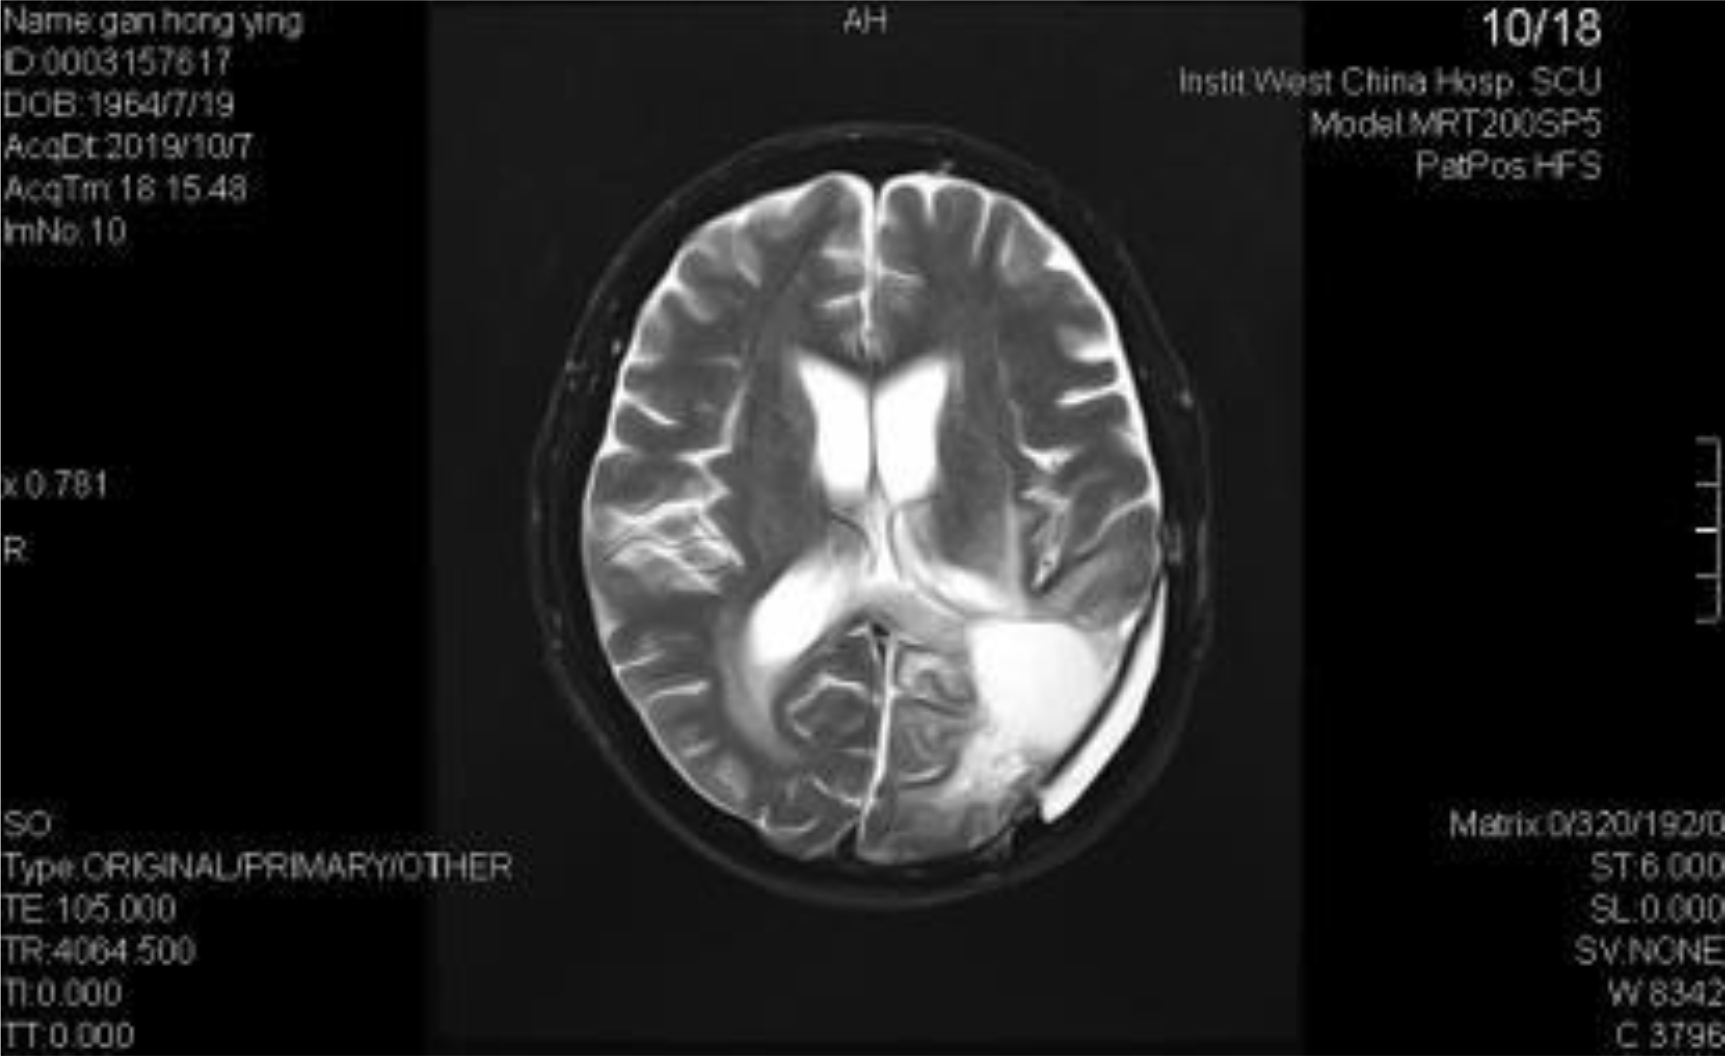

A 54-year-old female, developed a headache in December 2017. Examination showed that the left parietal occipital lobe occupied, and the first surgical treatment was performed, and the postoperative pathological diagnosis was glioblastoma. After operation, the patient received routine radiotherapy, 60Gy/33f, and temozolomide chemotherapy, 100mg/d (during radiotherapy), 300mg d1-5, q4w. In January 2019, the patient reexamined the MRI and found that the left temporal parietal space was occupied (Figure 1) and was operated again. The postoperative pathological diagnosis was still glioblastoma. The patient had occasional headache after operation, and the head MRI examination three months after operation indicated the progress of the disease (Figure 2). TTF was prepared to be used, and finally officially used the TTF treatment on July 4, 2019. The use time was relatively fixed, the utilization rate was 93%, and the compliance was good (Figure 3). During treatment, the patient developed allergic rash scattered on the scalp, mild itching, no ulceration and infection, and recovered quickly after topical application of antiallergic drugs. There had been several times that the patch temperature was too high, and the reasons are as follows: 1. The ambient temperature used was high (e. G. hot weather, direct sunlight, etc.). 2. The contact between the patch and the skin was not good. By instructing the patient to adjust the indoor temperature to about 24 °C, to use the headband or tape to strengthen the loose patch, to use the headband when sleeping at night, and to pay attention to clean the hair of the scalp every time, the situations had been significantly improved. Re-examination of the MRI in October 2019 showed that the condition was stable (Figure 4). Follow-up to 2020.1.23, the patient showed no symptoms of discomfort.

Figure 4